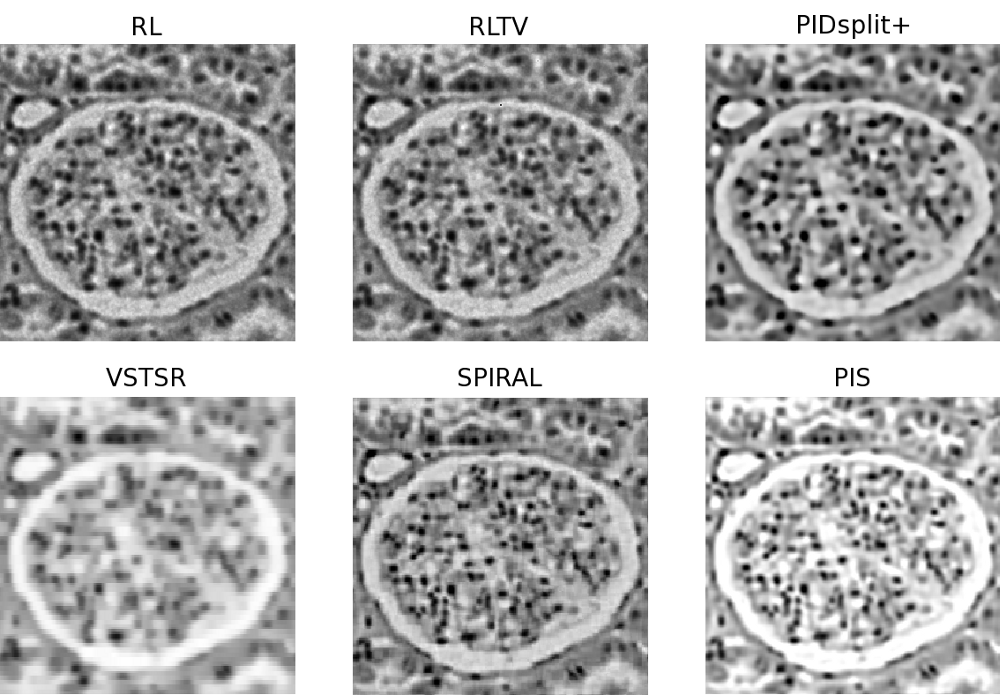

In this subsection, image reconstructions produced by the proposed and reference methods are tested using a microscopic image of glomerulus and the standard Shepp-Logan phantom, which are shown in Subplots A of Fig. 4 and Fig. 5, respectively. Similar to the case of sparse reconstruction, the images have been offset by a constant (background) value to give rise to different values of SNR. In particular, the value was adjusted to result in SNR equal to 32 (moderate noises) and 8 (strong noises). The original, blurred, and contaminated images of the glomerulus and Shepp-Logan phantom are summarized in Fig. 4 and Fig. 5 for all the tested values of and SNR.

For the case of glomerulus, the reconstructions obtained with the proposed and reference methods are summarized in Fig. 6 (for , SNR=32) and Fig.7 (for , SNR=8). Moreover, Fig. 8 and Fig. 9 depict the reconstructions of the Shepp-Logan phantom for the cases of , SNR=32 and , SNR=8, respectively. Analyzing these results, one can clearly see that, in all the above cases, the PIS algorithm yields reconstructions of superior quality (in terms of the resolution and contrast gain), as compared to the reference methods. This observation is further supported by the quantitative measures of Tables III and IV, which compare the estimation results in terms of the NMSE, SSIM index, and the number of iterations. As evidenced by the tables, the PIS method produces the lowest NMSE and the largest SSIM index among all the methods under comparison. As to the number of iterations required by PIS, one can see (with a reference to Table II) that the method has a computational complexity either comparable or lower than that of the reference methods.